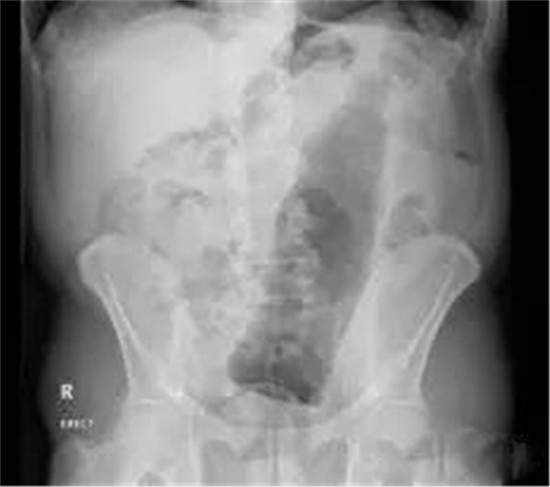

这是一个啤酒瓶。男性。

上面是一个啤酒瓶在大肠里。病人是男性。这是常见的肛门内异物。

这种情况,往往只要给病人打上全身麻醉,肛门松弛后,就可以用卵圆钳经过肛门把啤酒瓶拉出来。